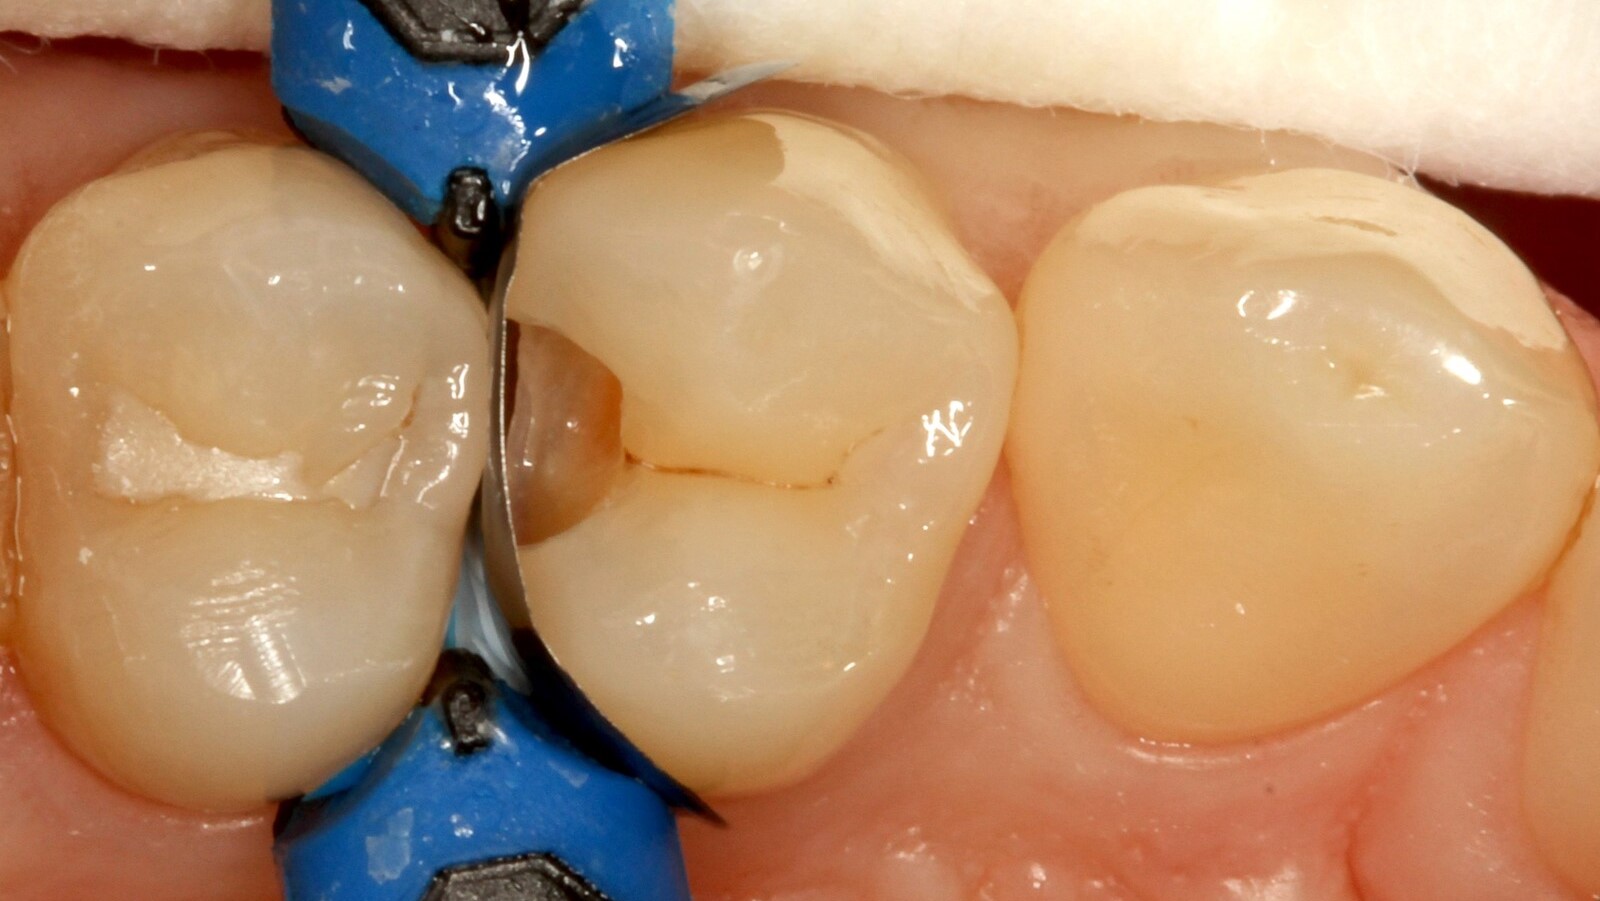

Prof. Dr. Claus-Peter Ernst, Zahnarzt und Lehrbeauftragter an der Universitätsklinik der Johannes Gutenberg-Universität in Mainz, verwendete Venus Bulk Flow ONE zur Restauration der Aproximalkaries eines Patienten an der distalen Fläche des ersten oberen linken Prämolaren. Dieser Fall veranschaulicht die Vielseitigkeit und einfache Anwendung von Venus Bulk Flow ONE, die es zu einer ausgezeichneten Wahl für eine Reihe von Indikationen macht, während es gleichzeitig eine außergewöhnliche Festigkeit und Ästhetik bietet.

Professor Ernst identifizierte zunächst die versteckte Karies und öffnete die kariöse Läsion, um dem Patienten das Problem zu veranschaulichen (Abb. 1-2). Anschließend exkavierte er die Karies, präparierte die Kavität und setzte eine Teilmatrize ein (Abb. 3), bevor er die Kavität mit Adhäsiv versiegelte (Abb. 4). In einem einzigen Schritt füllte er die Kavität mit Venus Bulk Flow ONE (Abb. 5). Nach der Fertigstellung polierte Prof. Ernst die Restauration (Abb. 6) und fertigte ein Kontrollröntgenbild an, das ebenfalls die hervorragende Röntgenopazität von Venus Bulk Flow ONE zeigt (Abb. 7).